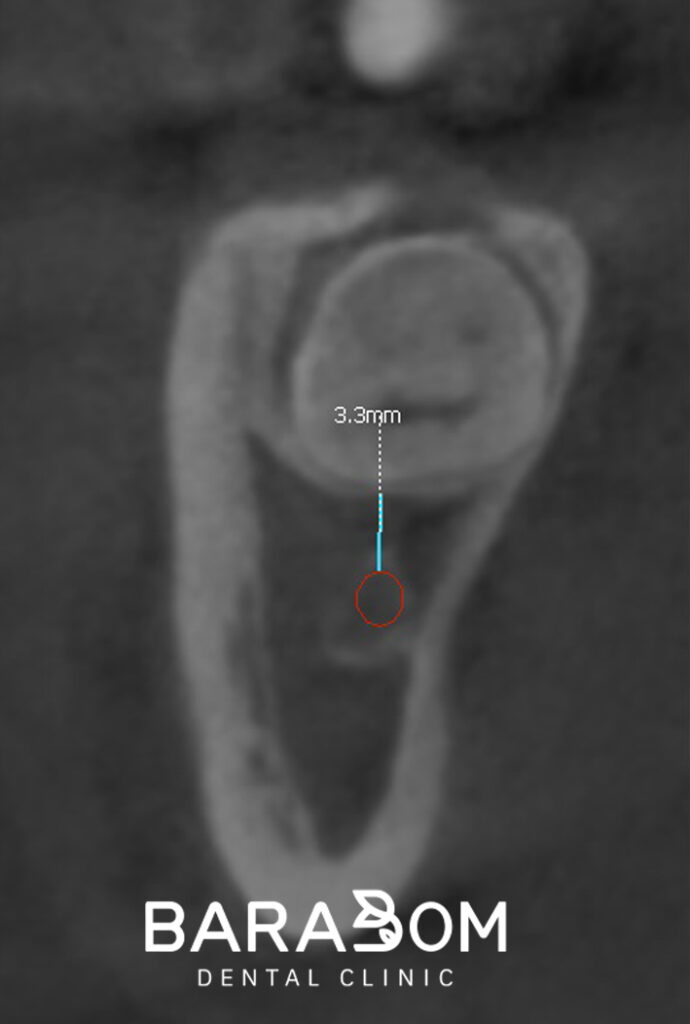

따라서, 3D-CT를 이용하여

각 부위별로 신경관과의 위치와

치근의 거리를 체크하여

진료 계획을 수립해야 됩니다.

하치조신경이 치아 하방 3mm 지점에 위치한다면

치아를 분할할 때 절삭 기구가

그 이상 내려가지 않도록 계획을 세웁니다.